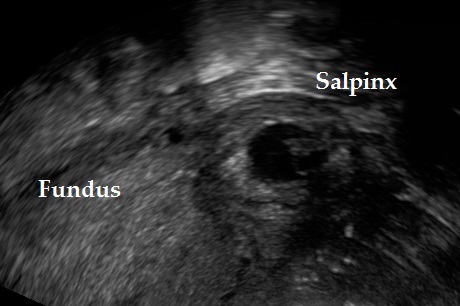

The following ultrasound criteria may be used for the diagnosis of interstitial pregnancy: empty uterine cavity, products of conception/gestational sac located laterally in the interstitial (intramural) part of the tube and surrounded by less than 5 mm of myometrium in all imaging planes, and presence of the ‘interstitial line sign’ (Elson CJ et al., 2016).